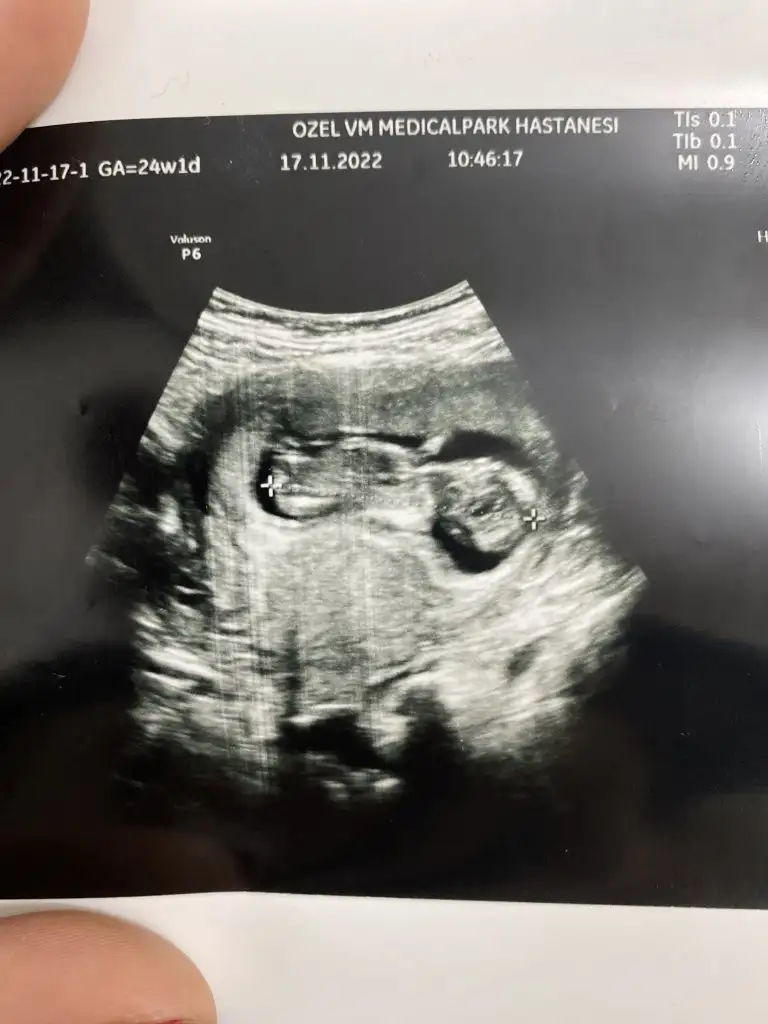

Nasıl durmuş anne karnında nasıl rahat şekle bakMerhaba arkadaşlar bu benim ilk hamileliğim o yüzden çok bilgim yok, bugün 12+4 de ikili ultrason yapıldı doktor cinsiyeti ne hissediyorsun dedi açıkçası içime herhangi bir şey doğmuyor yani kız yada erkek diye. Doktorum benim içime kız doğuyor haberin olsun dedi. Çok sevindim ama sonrasında kime söylesem hemen moda girme o sadece bi tahmin daha belli olmaz diyorlar. Erkek bebek kendini erken gösterir kızı 16. Haftaya kadar zor görüyorlar nasıl hemen söylemiş falan dedi yani şimdi kız dedi ama sonradan yanılma gibi bir payı var mı ? Çok mu erken cinsiyet için. Üstelik doktor çok sevindiğimi görünce yine de herkese söyleyip pembe şeyler alma hemen netleşsin , bana da bu zamanlar kız demişlerdi şimdi oğlum var dedi , ama 3 kez de üstüne basarak kız gibi görüyorum dedi. Açıkçası herkesin yorum yapması biraz böyle kafamı karıştırdı. Kız yada erkek asla farketmez sonuçta kızımda yok oğlumda ama insan ilk gebelik heyecanıyla bilip herkese söylemek istiyor sanırımböyle öğrenip sonradan cinsiyet değişen doktoru yanılan var mı ? Eskiler de çokmuş bu durum ama şimdi cihazlar çok gelişmiş olma diye umuyorum. Bu Arada fotoğrafta yüklüyorum belki sizde bi tahminde bulunursunuz

Teşekkür ederim kuzumNasıl durmuş anne karnında nasıl rahat şekle bakbüyük ihtimalle kız canım

Çevre herşeyi der, hayirlisi deyip geçinMerhaba arkadaşlar bu benim ilk hamileliğim o yüzden çok bilgim yok, bugün 12+4 de ikili ultrason yapıldı doktor cinsiyeti ne hissediyorsun dedi açıkçası içime herhangi bir şey doğmuyor yani kız yada erkek diye. Doktorum benim içime kız doğuyor haberin olsun dedi. Çok sevindim ama sonrasında kime söylesem hemen moda girme o sadece bi tahmin daha belli olmaz diyorlar. Erkek bebek kendini erken gösterir kızı 16. Haftaya kadar zor görüyorlar nasıl hemen söylemiş falan dedi yani şimdi kız dedi ama sonradan yanılma gibi bir payı var mı ? Çok mu erken cinsiyet için. Üstelik doktor çok sevindiğimi görünce yine de herkese söyleyip pembe şeyler alma hemen netleşsin , bana da bu zamanlar kız demişlerdi şimdi oğlum var dedi , ama 3 kez de üstüne basarak kız gibi görüyorum dedi. Açıkçası herkesin yorum yapması biraz böyle kafamı karıştırdı. Kız yada erkek asla farketmez sonuçta kızımda yok oğlumda ama insan ilk gebelik heyecanıyla bilip herkese söylemek istiyor sanırımböyle öğrenip sonradan cinsiyet değişen doktoru yanılan var mı ? Eskiler de çokmuş bu durum ama şimdi cihazlar çok gelişmiş olma diye umuyorum. Bu Arada fotoğrafta yüklüyorum belki sizde bi tahminde bulunursunuz